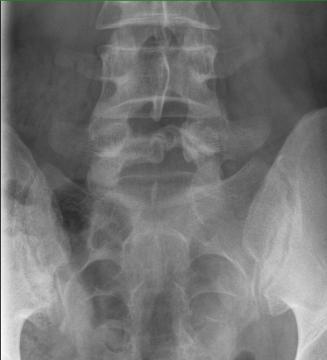

Zdravím,mam bolesti v oblasti panvy. Bol som na rontgene aj CT vyšetrení ohľadom chrbtice a teraz pri prehliadaní snímkov som si vsimol tmavších škvŕn. Myslel som ze je to chyba na smíku, ale je to aj z profilu môžete mi poradit o co sa jedná? Znamy tvrdil, že to moze byt zápal. Vďdaka za odpoved. (prikladam foto)

Myslíte ty dvě tmavší skvrny na levé straně snímku (při pohledu zepředu)?